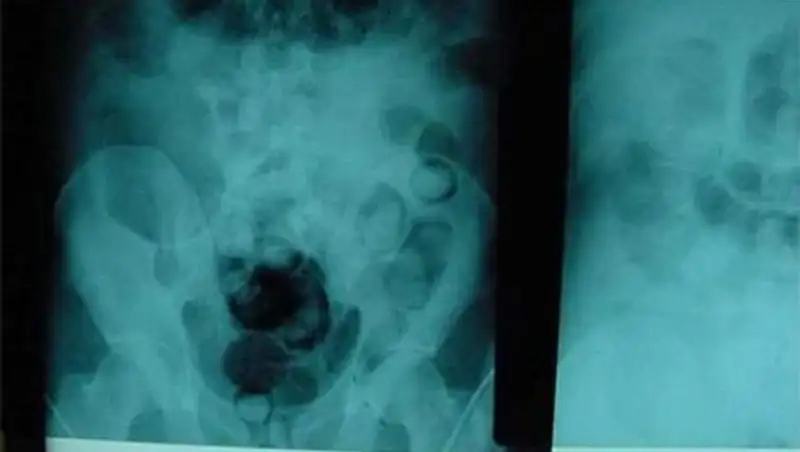

Гражданин Киргизстана итальянского происхождения по фамилии Мачелли ехал поездом «Бишкек-Екатеринбург». Ехал с багажом, который спрятал в надежном, как ему казалось, месте – в собственном желудке. В пассажире находились более 20 пакетиков героина общим весом 165 грамм.

Сотрудники департамента таможенного контроля уже знали, что один из пассажиров везет наркотики. И когда им сообщили, что некий мужчина в поезде вдруг начал галлюцинировать, они сразу направили итальянца в Областной медицинский центр. Врачи поставили диагноз: сильнейшее наркотическое отравление. Медики попытались промыть наркодиллеру желудок, но оказалось, что часть контейнеров с товаром уже находится в кишечнике мужчины. Пришлось срочно ложить неудачливого наркодиллера на операционный стол. Сейчас Марчелли находится в токсикологическом отделении больницы под конвоем. Следствию не удается опросить его, так как он все еще бредит. Врачи утверждают, что такие эксцессы с мужчиной происходят не в первый раз: у Марчелли «панцирный живот», такое случается, когда из-за частых порезов ткани обрастают хрящевой прослойкой.